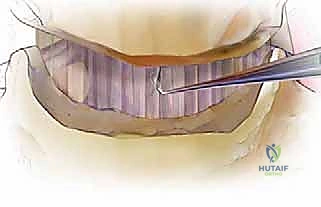

الخطوة 8: الإغلاق التجميلي

بعد التأكد من استقرار التثبيت وتوقف أي نزيف، تُعاد الأنسجة إلى مكانها الطبيعي بلطف، ويتم إغلاق الشق الجراحي بغرز تجميلية دقيقة تترك ندبة تكاد تكون غير مرئية بمرور الوقت.